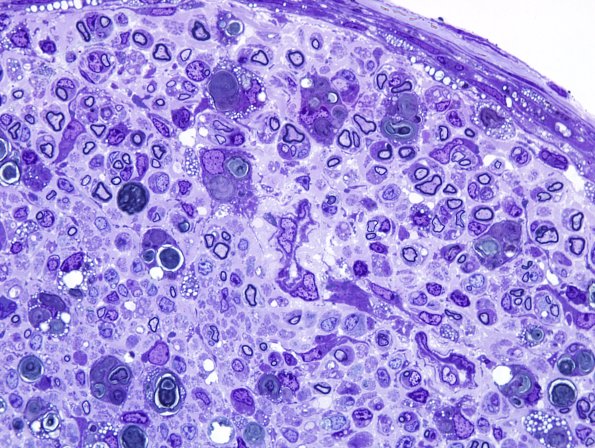

4 AXONAL DEGENERATION

2 Plastic Sections

28A5 Mouse Constriction Injury, distal sciatic (R13-233) Plastic 100X 4.jpg

Higher magnification of image #28A3.